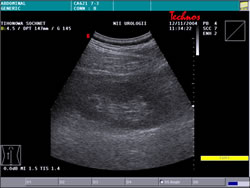

УЗИ: |

|